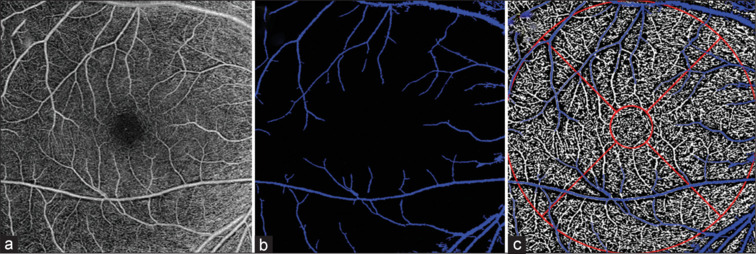

Purpose: To evaluate the effects of scanning tilt on the macular vessel density (VD) measurements in healthy subjects using optical coherence tomography angiography (OCTA).

Methods: OCTA imaging was performed on healthy subjects to acquire nasal and temporal oblique scans. Quantitative analyses included as follows: (1) VD in whole-image, annular, and quadrant regions of the superficial capillary plexus (SCP), deep capillary plexus (DCP), and choriocapillaris (CC) layer; (2) Foveal avascular zone (FAZ) parameters (area, perimeter, circularity index) in the SCP.

Results: Twenty-eight eyes of 28 healthy participants were included. Nasal inclination significantly affected VD measurement in the SCP temporal quadrant, DCP nasal/temporal/inferior quadrants, and all CC regions (all P < 0.05). Temporal tilt influenced VD measurements in all regions except the SCP superior and temporal quadrants (all P < 0.05). While FAZ area and perimeter remained unaffected by tilt, temporal tilt significantly reduced FAZ circularity (P = 0.022).

Conclusion: The tilt of the OCTA scan has different effects on the VD measurements of the whole, annular, and quadrant regions of macular layers and the FAZ circularity index.